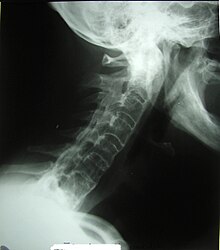

Veränderungen der Halswirbelsäule bei Morbus Bechterew